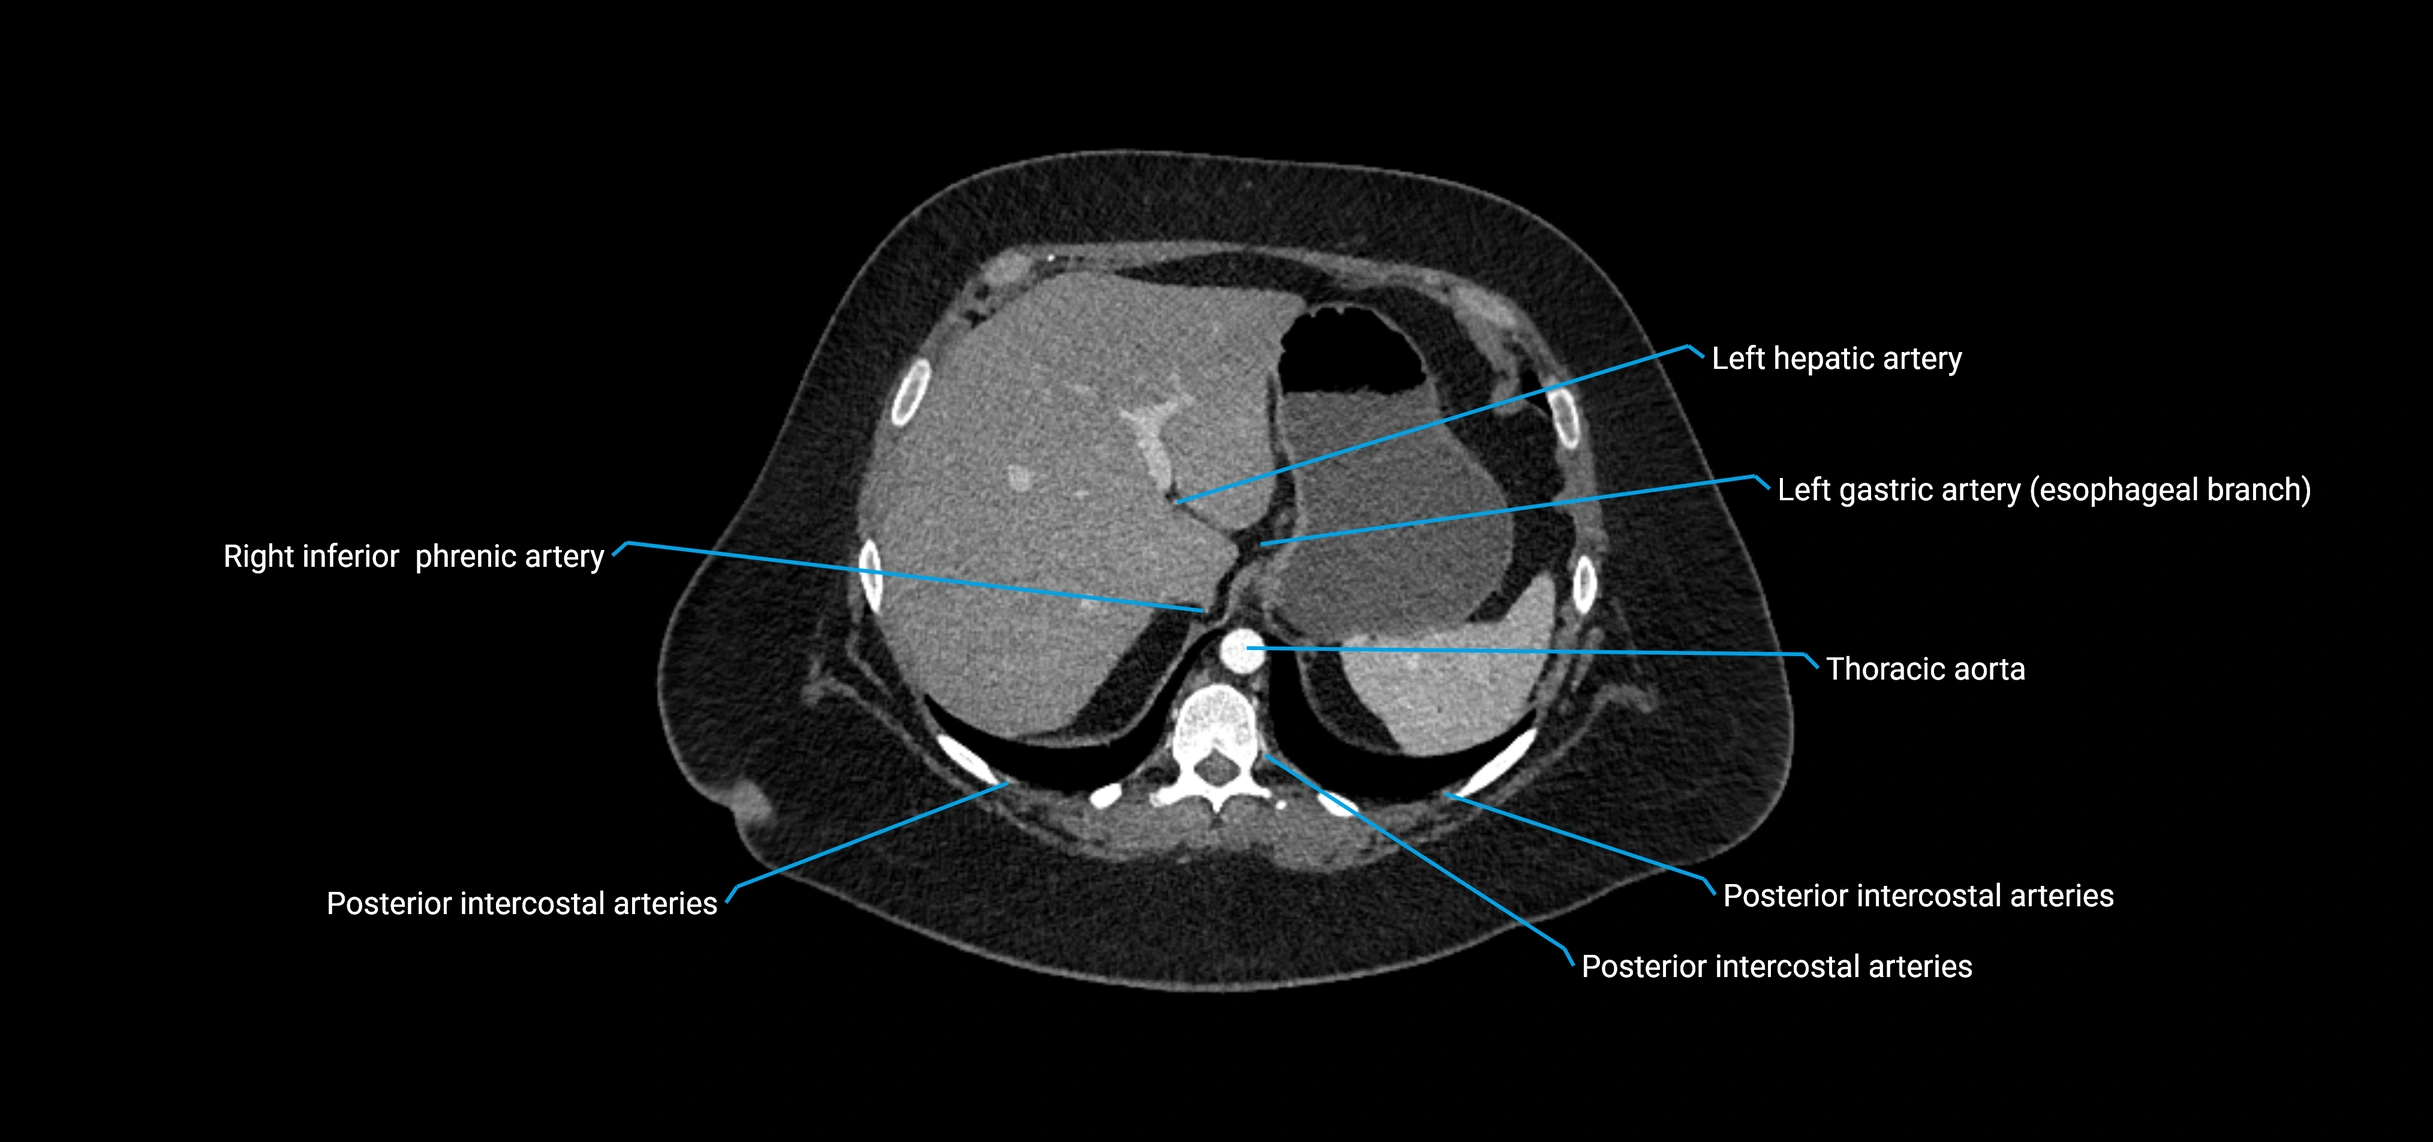

MRI Appearance

T1-weighted images:

• Flowing blood appears as a signal void (black lumen)

• Vessel wall appears as a thin hypointense rim; retroperitoneal fat enhances contrast

T2-weighted images:

• Lumen remains a signal void due to flow

• Adjacent edema, hematoma, or aneurysm wall thrombus may appear hyperintense

T1 Post-Contrast (Gadolinium-enhanced):

• Aortic lumen enhances brightly and homogeneously

• Clearly demonstrates aneurysm, stenosis, dissection, mural thrombus, or aortic wall enhancement in vasculitis

MRA (Magnetic Resonance Angiography):

• Contrast-enhanced MRA provides high-resolution imaging of the aorta and its branches

• Allows 3D reconstruction of visceral, parietal, and terminal branches

• Excellent for evaluating aneurysm size, dissection flap, stenosis, or preoperative planning

• Non-invasive alternative to conventional angiography